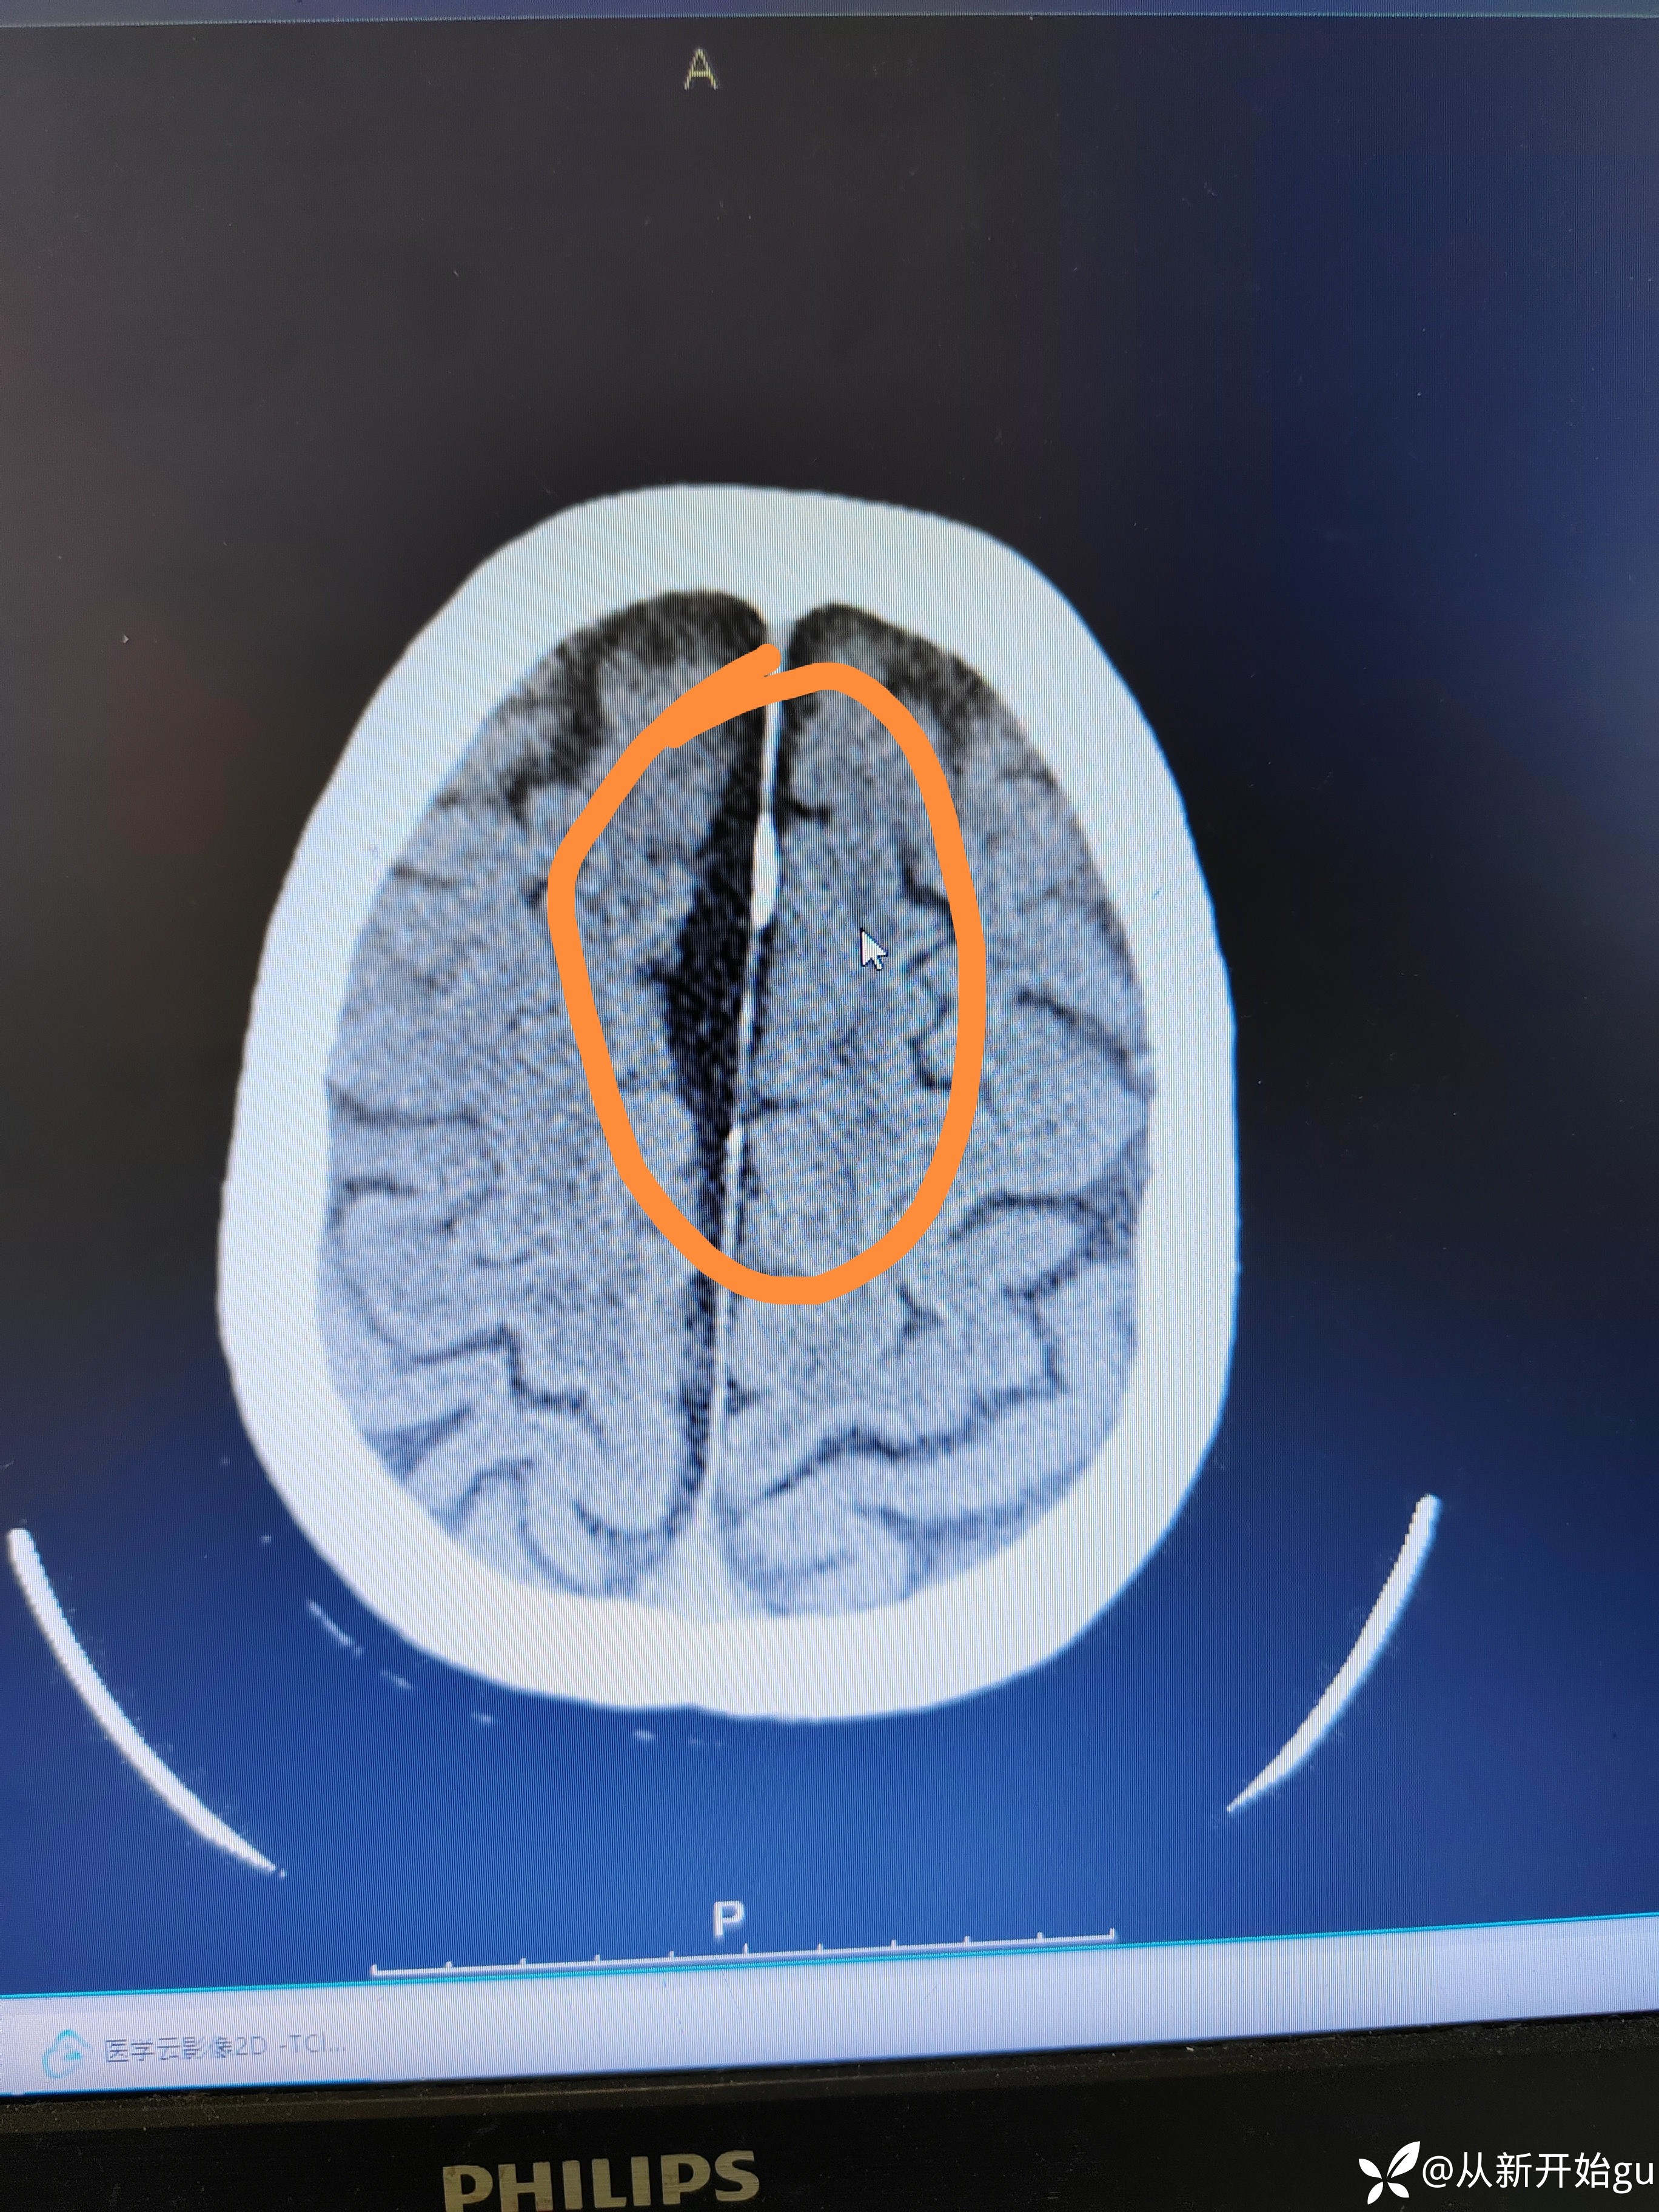

神经内外最近热帖已更新